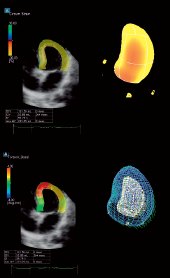

Технология 3D Wall Motion Tracking - сердце, объемная трехмерная (3D) структура, а значит и движение сердца и смещение спекл- шумов происходит в трёх плоскостях.

3D-технологии используются для получения полного объема данных о структурном и функциональном состоянии левого желудочка. Чтобы рассчитать движение стенки в трех измерениях, требуется хорошо сбалансированный набор данных с точки зрения пространственного и временного разрешения.

Кроме оценки деформации миокарда в 2D WMT режиме можно оценить следующие объемы:

• КДО - конечный диастолический объем

• КСО - конечный систолический объем

• ФВ - Фракция выброса

• ММЛЖ - масса миокарда левого желудочка